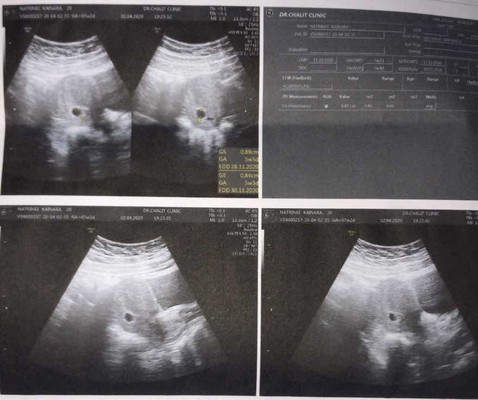

ถามหน่อยนะคะท้องแรกค่ะ

ตอนนี้เพิ่ง7สัปดาห์ค่ะ แบบนี้คือมีน้องมั้ยคะ หรือเป็นแค่ถุงเฉยๆ ตอนนี้กังวลกลัวเป็นท้องลมค่ะ ดูไม่ค่อยออกด้วย คุณหมอบอกอีก2อาทิตย์มาซาวด์อีกครั้งตอนนี้ยังไม่ค่อยเห็นพอดีตอนนั้นตื่นเต้นไปหน่อยเลยลืมถามว่าไม่เห็นเด็กหรือว่ายังไม่เห็นอวัยวะเฉยๆ